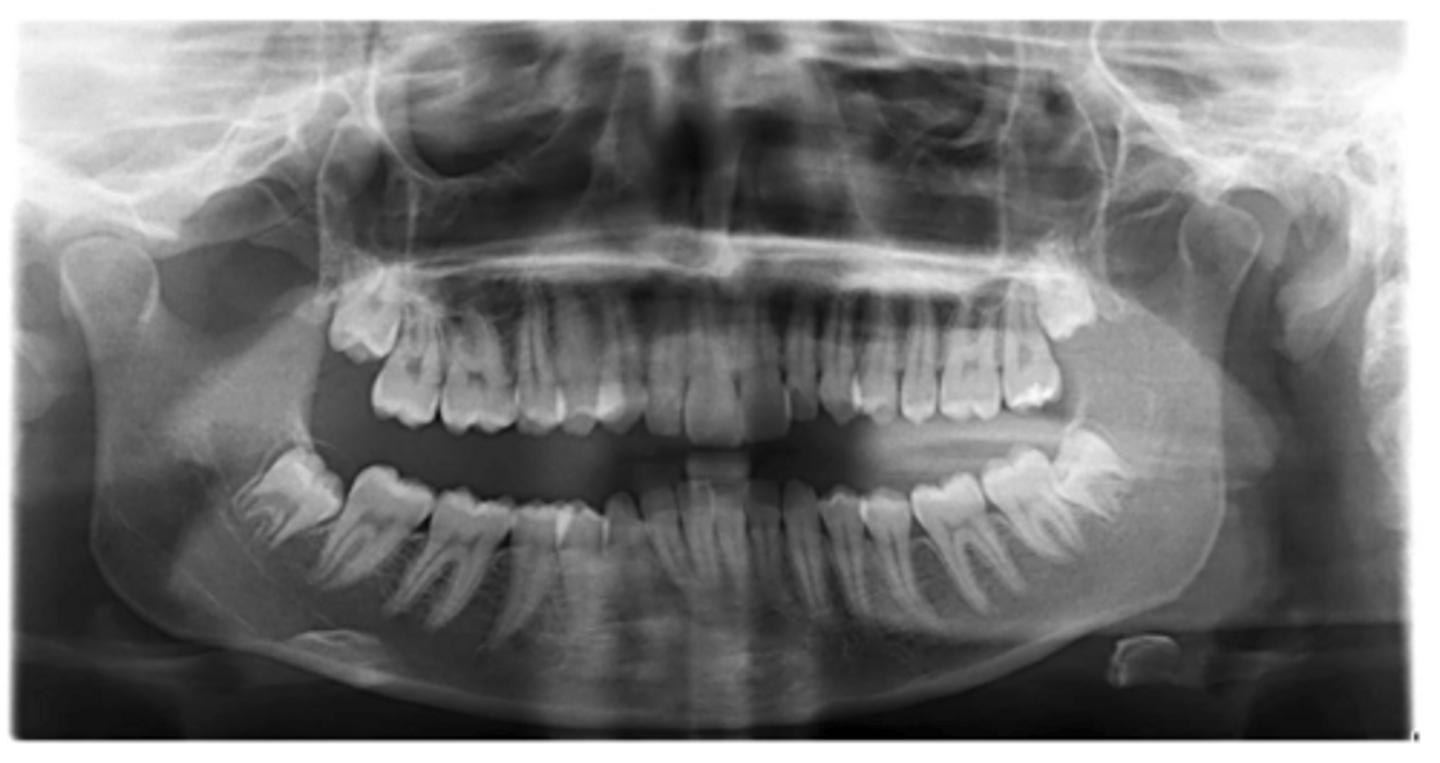

Right primary canine

Are there retained primary teeth?

Yes

Are there any impacted teeth?

Are the condyles symmetrical?

Is there a dilacerated root?

No

The mandibular left side has normal premolar/canine eruption, but the rigth side is abnormal.

Is the eruption pattern of this patient normal or not?

Are there any supernumerary teeth?

Are there any retained primary teeth?

Not at this stage

Are there impacted teeth?

Yes, within the range of normal

Symmetric condyles?

Yes - maxillary first molar

Dilacerated roots?

Yes - laterals

Are there congentially missing teeth in the maxillary arch?

Yes - an incisor

Are there congenitally missing teeth in the mandibular arch?

Yes - upper right near the premolar

Any impacted teeth?

Can't see, so can't say

Yes - #2, also #27?